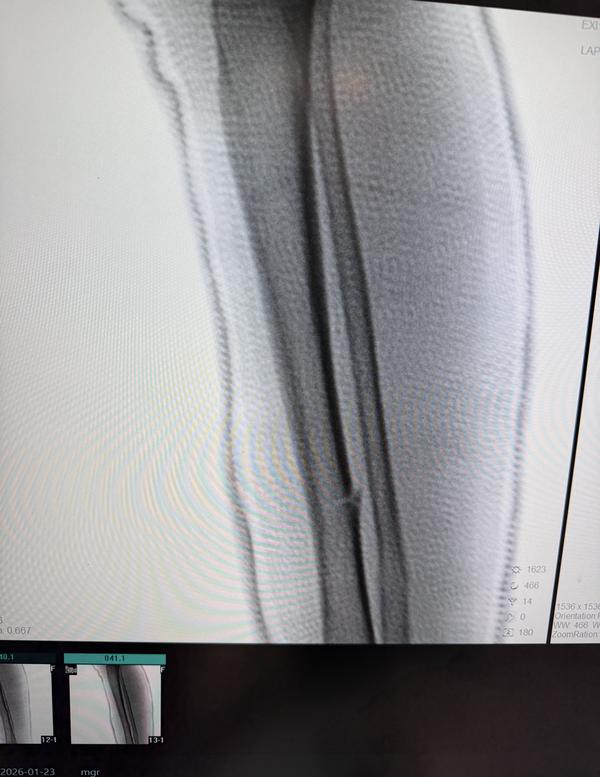

CLOSED REDUCTION AND ABOVE KNEE CAST OF 5 YEAR OLD CHILD

View DetailsCLOSED REDUCTION AND ABOVE KNEE CAST OF MIDSHAFT TIBIA FIBULA FRACTURE

View DetailsRIGHT MIDSHAFT TIBIA FIBULA FRACTURE OF 5 YRS OLD GIRL CHILD , CLOSED REDUCTION AND ABOVE KNEE CAST ...